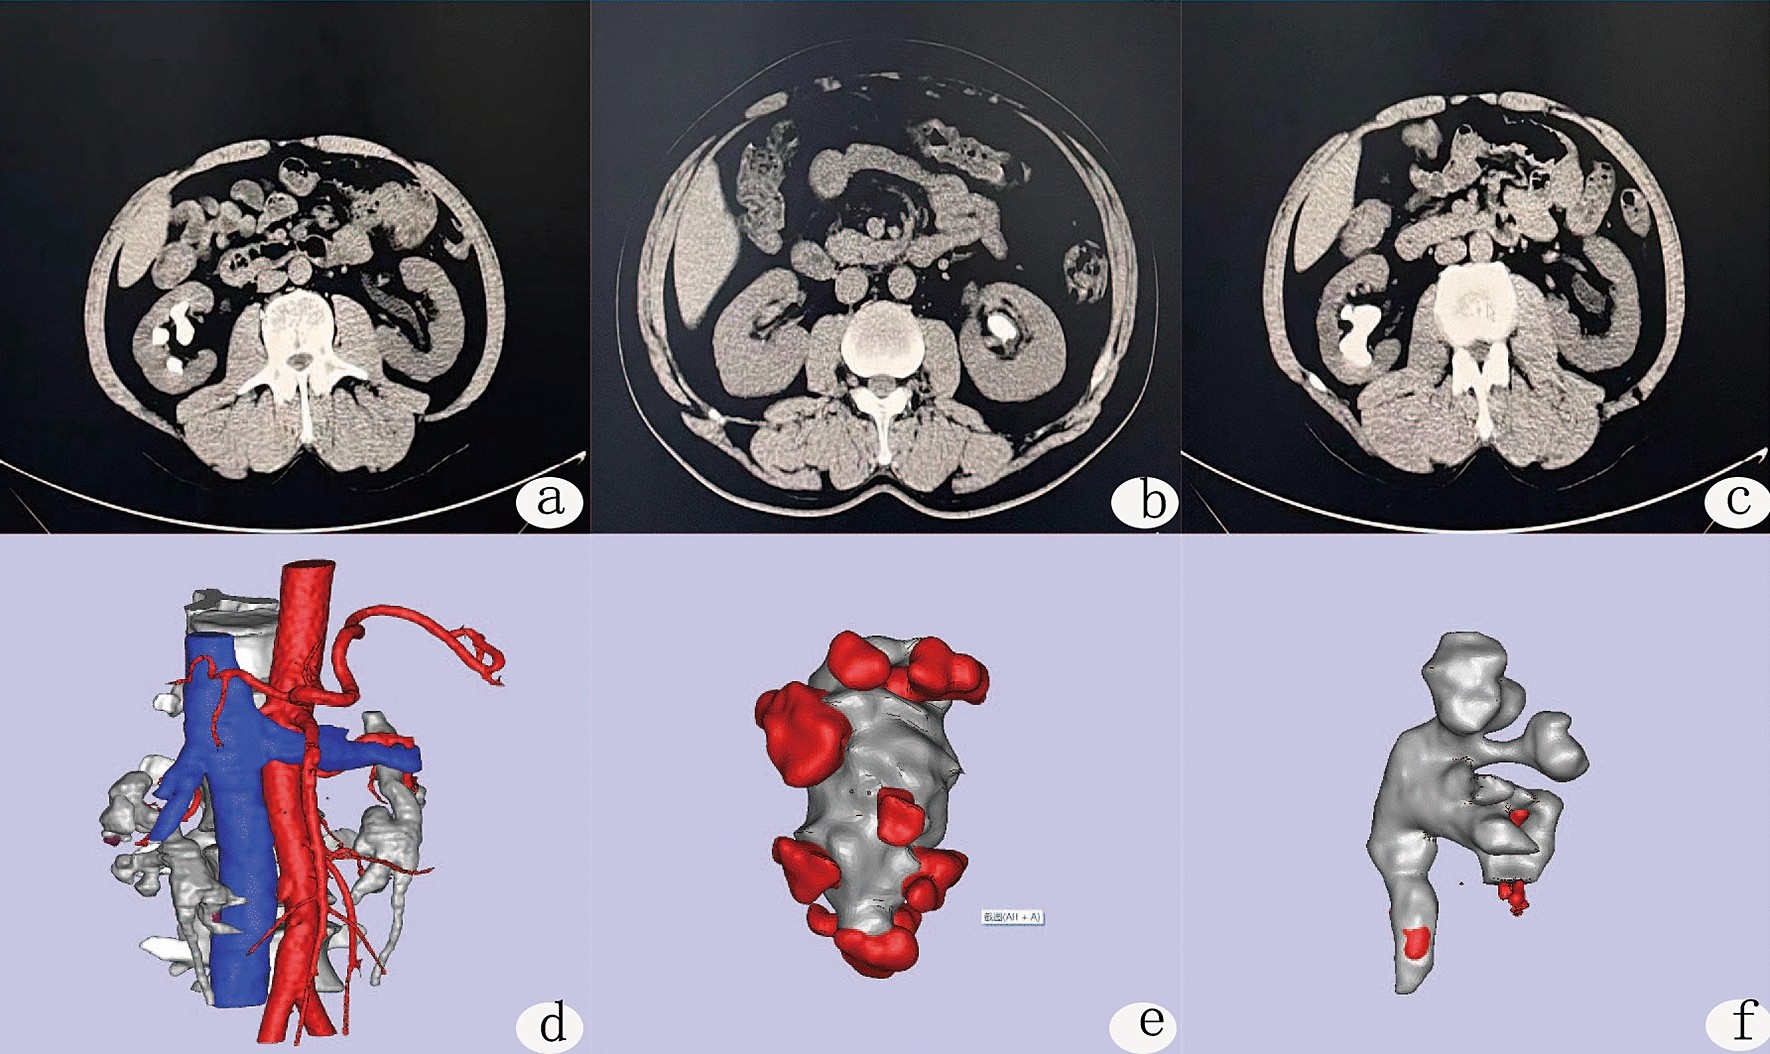

CT and three-dimensional reconstruction of different parts of the kidney. (a–c) Typical preoperative CT of the patients; (d–f) three-dimensional reconstruction images of different parts of the kidney. (d) Distribution of renal blood vessels, (e) renal pelvis and calculi, (f) three-dimensional reconstruction of the renal pelvis and the size and location of the calculus.